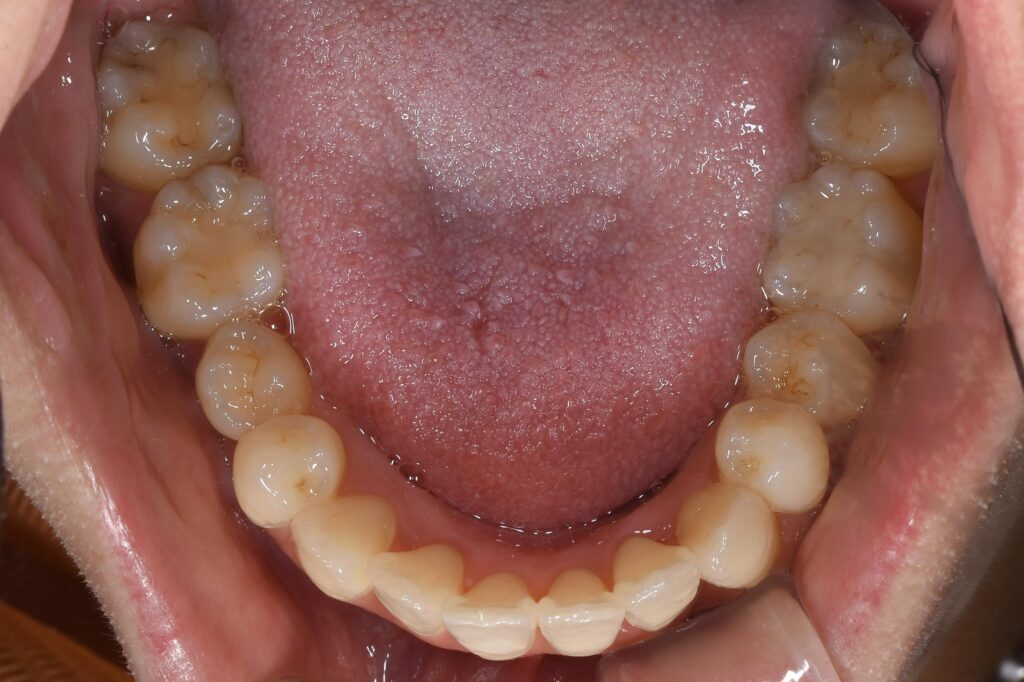

その上で矯正開始1年後の状態です。

【矯正開始1年後】

いかがでしょうか。

結論として、非抜歯(抜歯は行っていません)でここまで歯並びを改善することができました(^^)/

患者様にもとても喜んで頂けました!

今回このように抜歯を行わず改善できたのも、インビザラインのコンピューターシュミレーションがあってこそでした。このように、抜歯が必要か抜歯を回避して配列が可能かを事前にシュミレーションできることは、本当に治療の幅を広げてくれています。